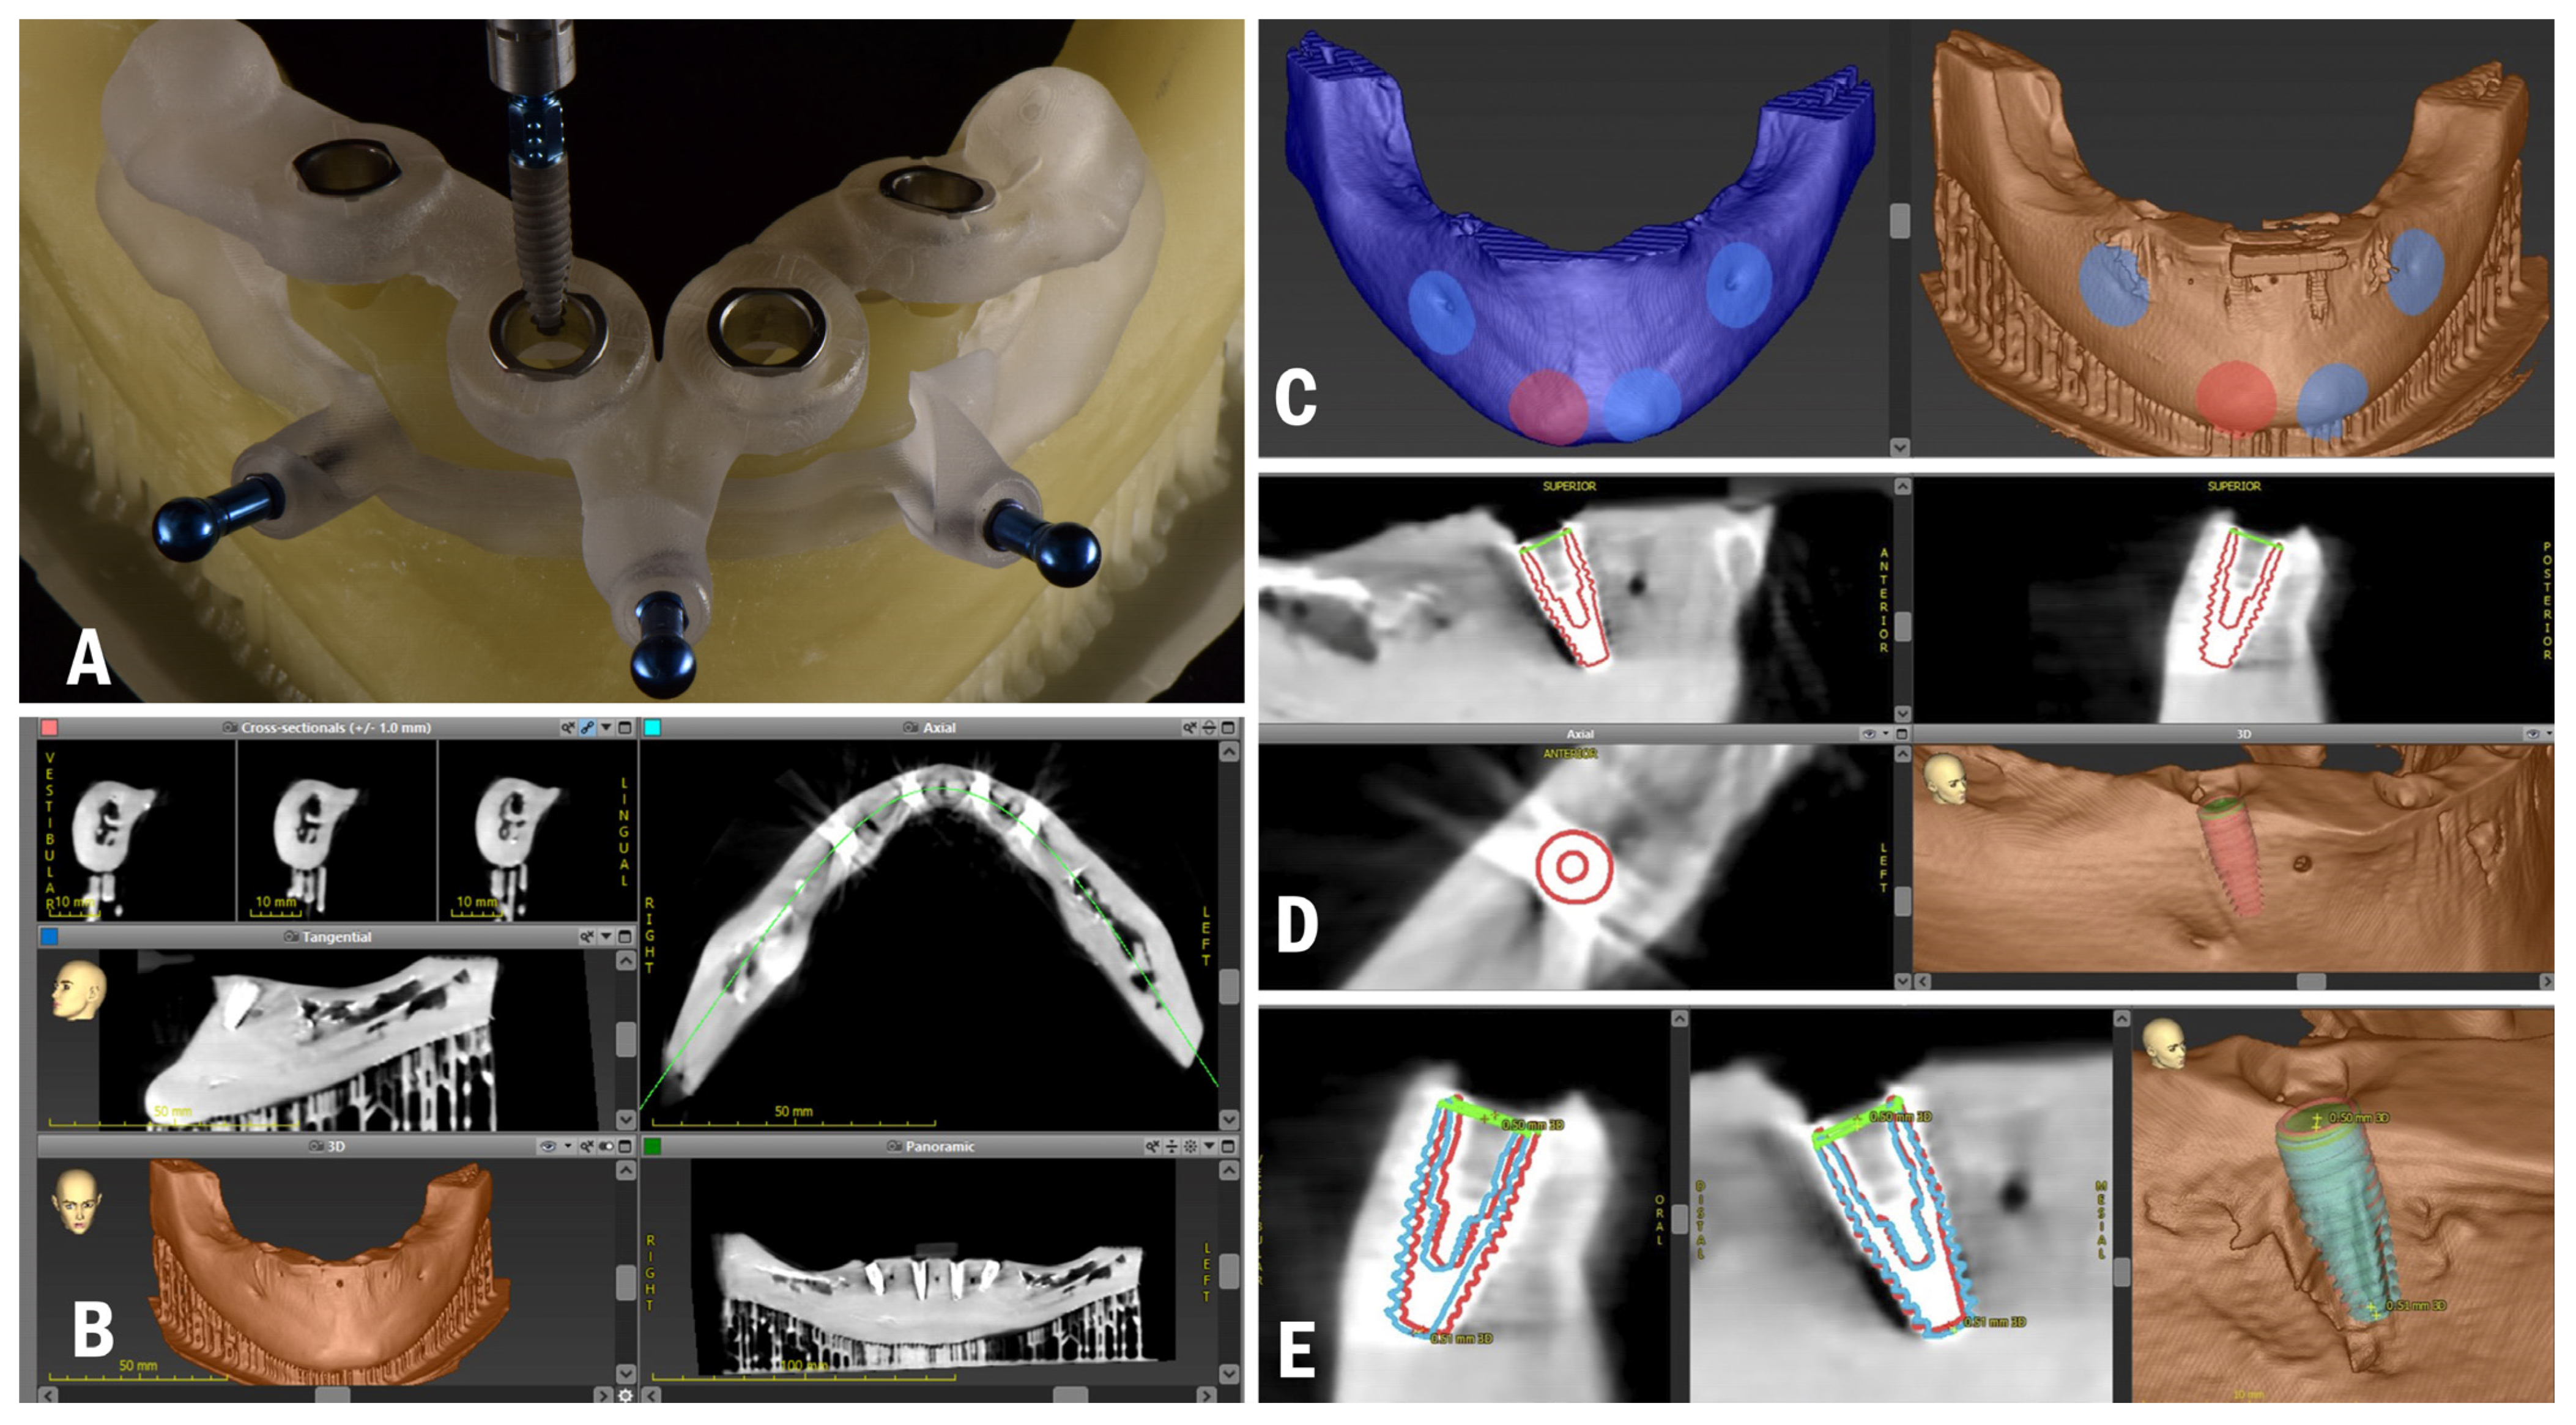

2. Materials and Methods

2.1. Planning and Surgery

3.2. In Vitro Treatment Evaluation